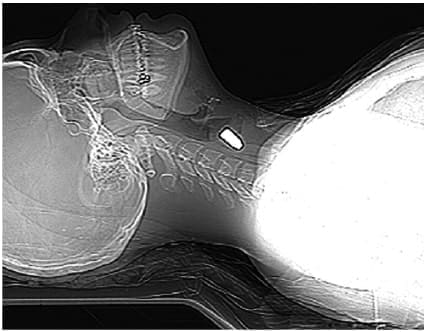

Por tratarse de un trauma penetrante de cuello secundario a un proyectil de arma de fuego y por su localización, se consideró que tenía compromiso de planos profundos y una alta probabilidad de lesión orgánica (figura 2).

Figura 2. Proyección radiográfica lateral en decúbito supino, visualizando el proyectil de arma de fuego en el cuello, a nivel del quinto cuerpo vertebral (C5), con trayecto oblicuo y descendente en dirección al tórax y localizado en los tejidos blandos. Fuente: los autores.